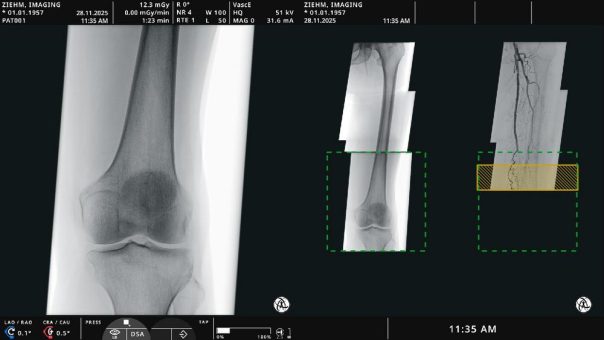

Ziehm Imaging stellt auf dem diesjährigen European Congress of Radiology (ECR 2026) erstmals die neuesten Innovationen Endovascular Navigation1 Peripheral2 und PositionPilot2 der Öffentlichkeit vor. Nach der Einführung von Endovascular Navigation Aorto-iliac im vergangenen Jahr präsentiert Ziehm Imaging nun die endovaskuläre Navigationssoftware für periphere arterielle Verschlusskrankheiten. Die innovative Navigationslösung für die unteren Extremitäten ist in denRead more about ECR 2026: Ziehm Imaging präsentiert neue OP-Tisch-Steuerung und innovative endovaskuläre Softwarelösung[…]